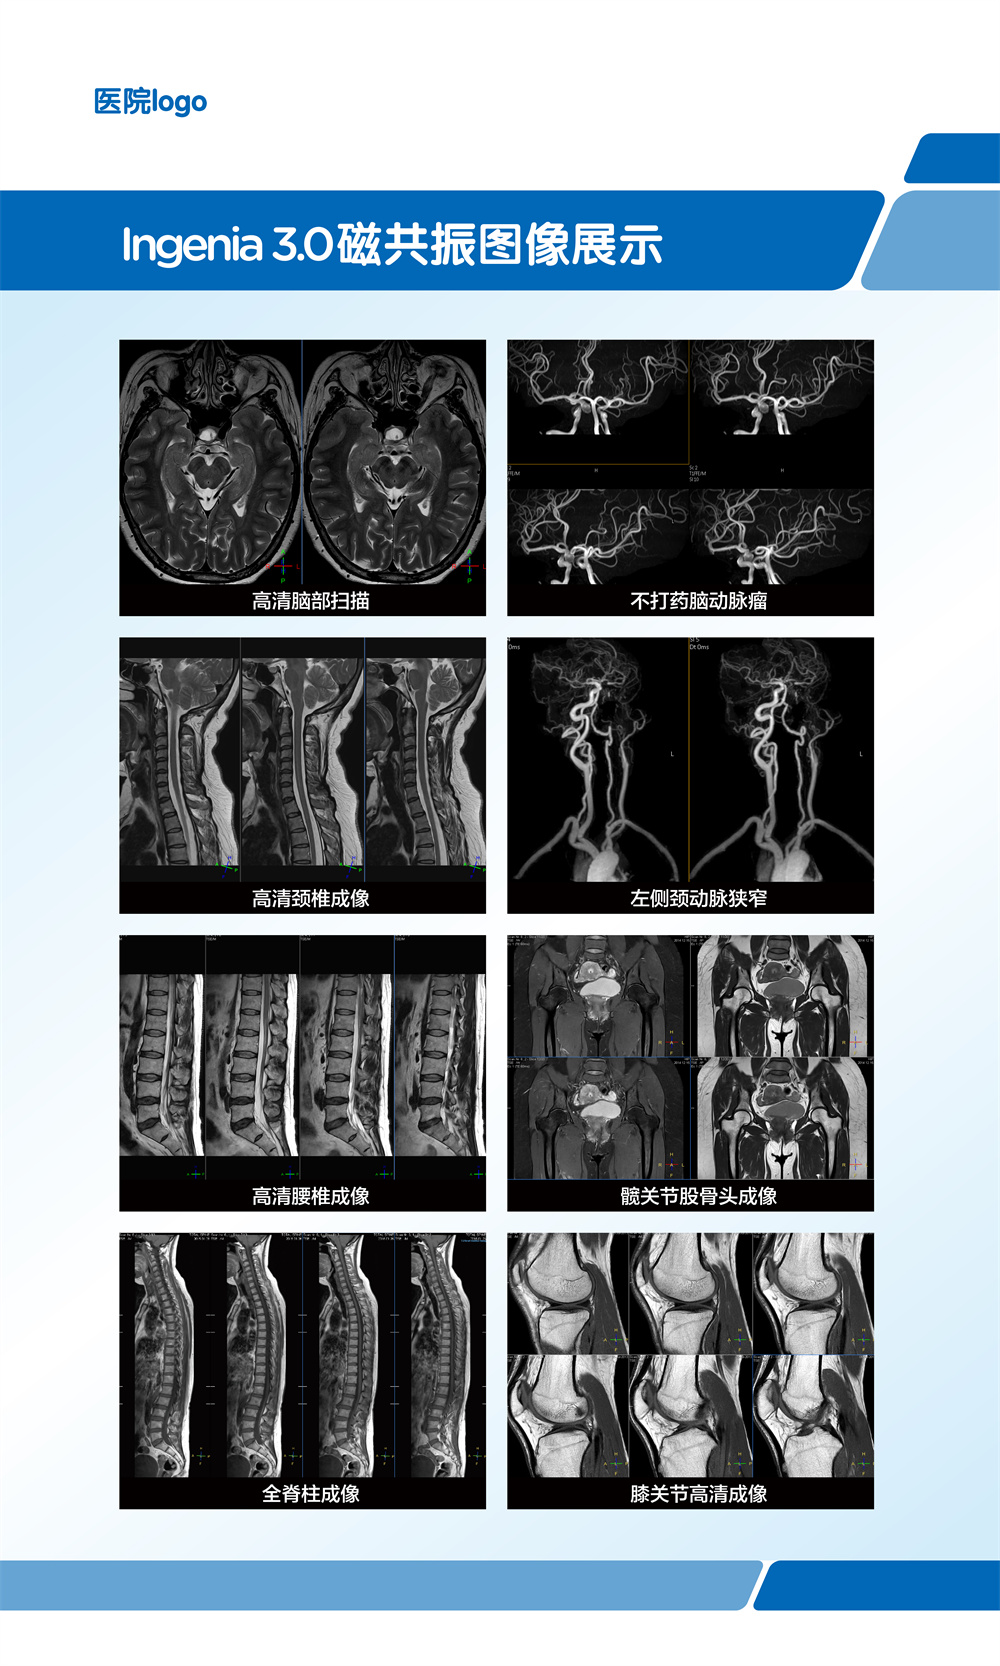

飞利浦大孔径光速Ingenia 3.0T磁共振是业内唯一同时具备"全数字高清成像平台和四维多源射频发射成像平台"的高端3T磁共振,具有病人检查舒适,扫描速度快,图像分辨率高的特点。在神经系统,骨肌系统,体部系统包括心脏和腹部等都有良好的应用和独到优势,为疾病的诊断及治疗提供更可靠、更丰富的信息,对于脑卒中和胸痛等中心的建设起到重要的作用。设备具备飞利浦独有的全数字线圈,可以实现三维全心不打药冠脉成像,无电离辐射和造影剂过敏风险,精准显示冠脉狭窄,有效排查临床无意义的冠脉狭窄(准确度达90%)。

磁共振冠状动脉检查无辐射,无需对比剂,对于缺血性心脏病,可以一次成像完整显示全心冠脉,便于直观诊断冠脉各分支情况。

亮血:血管狭窄筛查。黑血:血管壁斑块成像。

第三代无损加速磁共振成像-压缩感知(CS-SENSE),最快 32 倍加速,已将绝大部分临床成像转化为快速高清容积扫描。